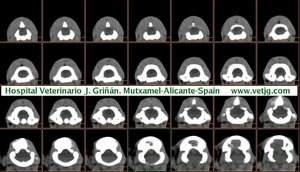

imágenes de TC en el gato | |||||||||||

Tomografía computarizada helicoidal |